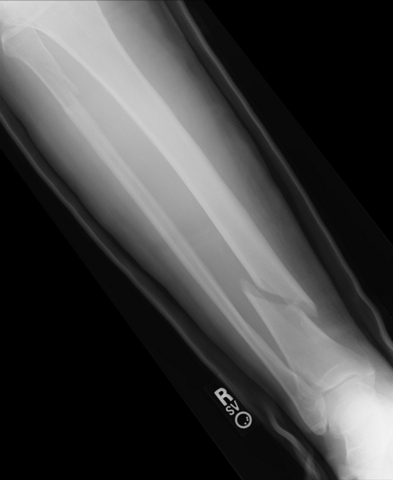

• Ouch!

Ouch!

As I was playing soccer I was fighting for a ball and I fell down breaking my leg. Because of the way my leg broke, I had to have surgery.